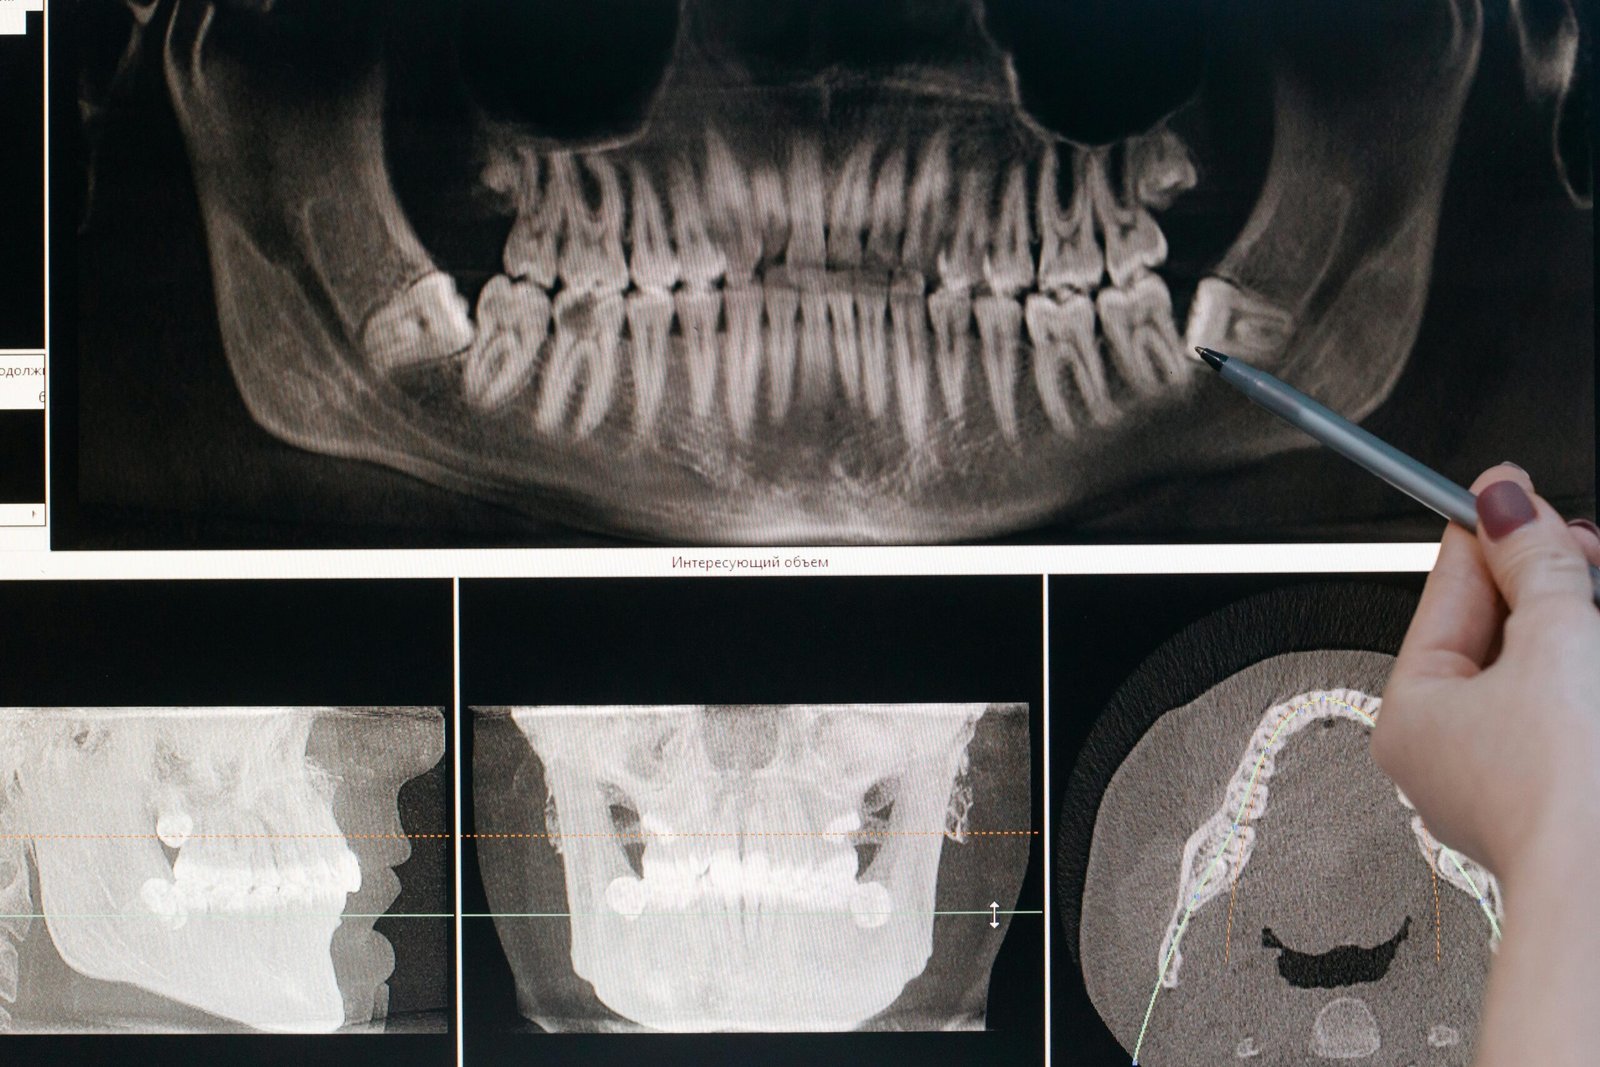

أما بالنسبة لاختراق اللويحات، فإن الأحماض الناتجة عن البكتيريا تؤدي إلى تآكل المعادن في الطبقة الصلبة الخارجية للأسنان، والتي تُعرف بالمينا. ينتج عن هذا التآكل ظهور فتحات صغيرة في المينا، مما يشير إلى بداية تكون التجاويف. بمجرد أن تتضرر المينا، يمكن للأحماض والبكتيريا أن تنتقل إلى الطبقة التالية من الأسنان، وهي العاج. هذه الطبقة أكثر ليونة من المينا وأقل قدرة على مقاومة الأحماض، مما يجعل الأسنان أكثر عرضة للحساسية.

مع استمرار الأذى، تنتقل البكتيريا والأحماض إلى داخل السن، حيث تصل إلى لب السن الذي يحتوي على الأعصاب والأوعية الدموية. نتيجة للبكتيريا، يصبح لب السن متورمًا ومتهيجًا. ونظرًا لأن السن لا يحتوي على مساحة كافية للتورم، يضغط التورم على العصب مما يسبب الألم. في بعض الحالات، قد يمتد الألم والتلف إلى العظم المحيط بالسن، مما يؤدي إلى ترقق العظم حوله وقد يؤثر أيضًا على الأسنان المجاورة .مصادر للاطلاعhttps://my.clevelandclinic.org/health/diseases/10946-cavities